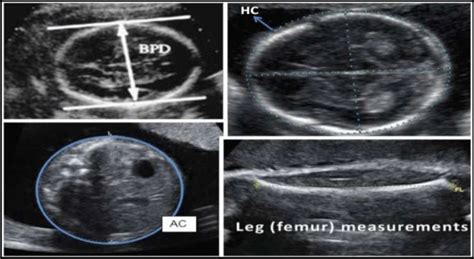

• BPD (Biparietal Diameter): This measures the distance across your baby’s head from one side to the other. It’s a crucial measurement for estimating gestational age and assessing head development. Think of it as the width of the baby’s head.

• HC (Head Circumference): As the name suggests, this is the measurement around your baby’s head. It’s another important indicator of head size and brain development. HC is often used together with BPD to get a comprehensive view of the baby’s head.

• AC (Abdominal Circumference): This measures the circumference of your baby’s abdomen (belly). It’s a key indicator of fetal weight and helps assess the growth of the baby’s abdominal organs, like the liver and stomach. This measurement can be more variable than head measurements, since it can fluctuate depending on the baby’s position and when they last ate.

• FL (Femur Length): This measurement is of the length of your baby’s thigh bone (femur). It’s used to estimate fetal size and can be a good indicator of overall skeletal development. It can also help confirm the gestational age.